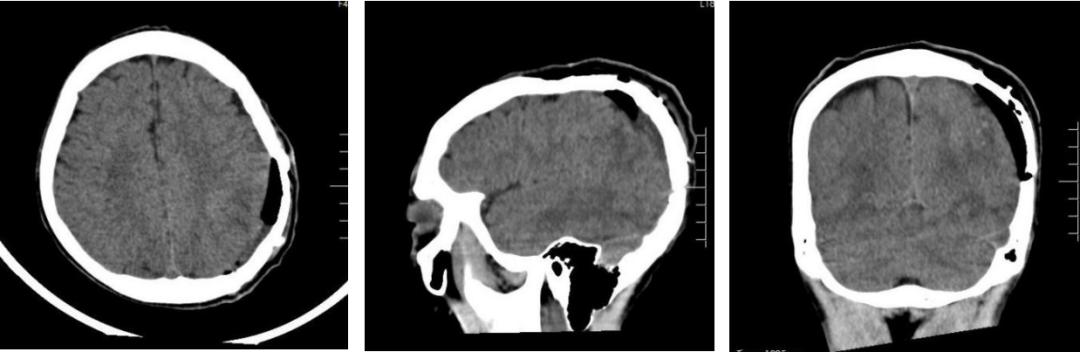

术后第二天情况,小军可简单对答,四肢肌力、活动正常,很快就顺利出院了。

▲术后复查CT所见:左侧顶部凹陷骨折整复+硬膜外血肿清除术后改变。